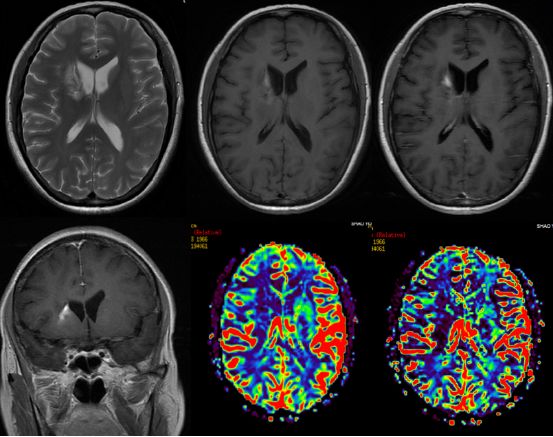

术后患者恢复良好。因病理诊断考虑脱髓鞘病变,故建议患者回当地医院神经内科继续治疗,并定期复查。经电话随访,患者在当地医院予以糖皮质激素等对症治疗,具体剂量不详。1月后来浙江大学医学院附属第二医院复诊。复查头颅磁共振增强扫描+灌注成像提示:右侧尾状核头部占位,周围轻度水肿, PWI示病灶区灌注减低,增强后病灶示有不均匀强化,余双侧大脑半球对称,中线结构无明显移位。意见:右尾状核头部病变活检术后改变,较前片病灶缩小,结合病灶低灌注,倾向非肿瘤性病变。(图4)

图4.术后1月患者复查磁共振增强+灌注扫描,提示增强后病灶较前有所缩小,占位效应减轻,病灶灌注成像未见高灌注。